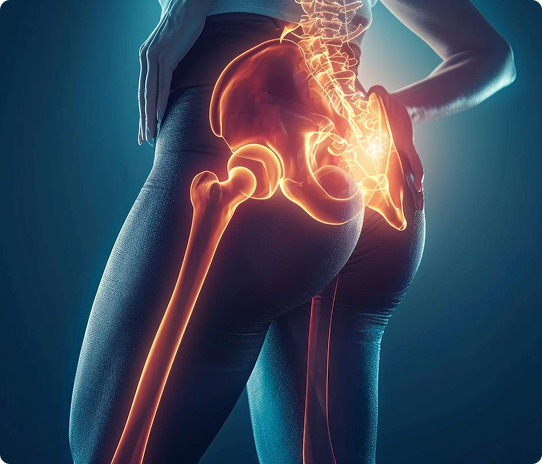

If you have deep pain in the lower back, buttock, or hip that worsens with standing or climbing stairs, the cause may be Sacroiliitis inflammation of the sacroiliac (SI) joint, where the spine meets the pelvis.

The sacroiliac joints sit on either side of the spine, connecting the sacrum

(the base of your spine) to the iliac bones of your pelvis.

When irritated or inflamed, they can produce deep, localized pain that may radiate to the buttock or thigh.

Sacroiliitis can cause pain patterns often confused with sciatica or hip disorders. Typical features include:

Deep aching pain in the lower back, buttock, or hip (often one-sided)

Pain that worsens with standing, stair climbing, or sitting for long periods

Discomfort rolling over in bed or getting out of a car

Occasional radiation of pain into the thigh (but rarely below the knee)